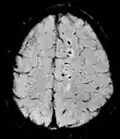

Neuroimagem

A ressonância magnética é a ferramenta investigativa de escolha para cânceres neurológicos, pois tem melhor resolução do que a TC e oferece uma melhor visualização da fossa posterior. O contraste fornecido entre matéria cinza e branca torna a ressonância magnética melhor opção para muitas condições do sistema nervoso central, incluindo doenças desmielinizantes, demência, doença cerebrovascular, doenças infecciosas e epilepsia.[30] Uma vez que muitas imagens são retiradas em milisegundos, mostra como o cérebro responde a diferentes estímulos, permitindo que os pesquisadores estudem as anormalidades cerebrais funcionais e estruturais em distúrbios psicológicos.[31] A RM também é utilizada na cirurgia estereotáxica guiada por MRI e radiocirurgia para o tratamento de tumores intracranianos, malformações arteriovenosas e outras condições tratáveis cirurgicamente usando um dispositivo conhecido como N-localizer.[32][33][34][35][36][37][38][39][40][41][42][43][44][45]